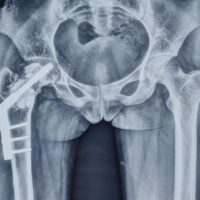

Despite the edge-to-edge reinforcement using horizontal mattress sutures and simple interrupted sutures with monofilament suturing material, there were concerns regarding potential rupture due to the fragility of the delicate tissue. Consequently, a segment 1/3 in thickness and 20 mm in length was harvested from the proximal part of the right EHL (Fig. 4b) and grafted onto the connected part for reinforcement (Fig. 4c). The schematic diagram of the process is shown (Fig. 4d). The safety of early passive motion was ascertained through intraoperative assessment of gentle passive motion. Neutral alignment has been achieved through tendon lengthening and is expected to be maintained with external fixation. Furthermore, taking into account the preservation of tendon gliding function, the prevention of contracture risk, and the potential impact of pin site infection on the graft, it was deemed preferable not to perform bony stabilization using K-wires or similar methods. Postoperatively, a short splint was applied for 3 weeks. Following this period, the patient was instructed to commence range of motion (ROM) training and was advised to use the offloading shoe, OrthoWedge (DARCO, Huntington, WV) for an additional 3 weeks to avoid loading stress on the right toe. After 6 post-operative weeks, the patient was allowed to resume normal ambulation without OrthoWedge. The patient’s activities of daily living showed steady improvement. At the 1-year post-operative follow-up, the patient’s severe right hallux pain decreased from a visual analog scale score of 10–2, with temporary alleviation to 0. Moreover, the patient achieved a smooth right hallux ROM, progressing from a hyperdorsiflexed stiff hallux condition at 20° to a smooth hyperdorsiflexion of 25° and a smooth active plantar flexion of 5°, without recurrence of the previous condition. No recurrence of hyperdorsiflexion has been observed on follow-up plain radiograph (Fig. 5).

Figure 5: The appearance of the right metatarsophalangeal joint 1 year after the surgery. (a) Maximum active dorsiflexion is confirmed. (b) Maximum active plantar flexion is confirmed. (c) Overall appearance of the right foot. There is no recurrence of hallux hyperdorsiflexion and stiffness. (d) The hallux was observed to maintain a neutral alignment on plain radiograph.